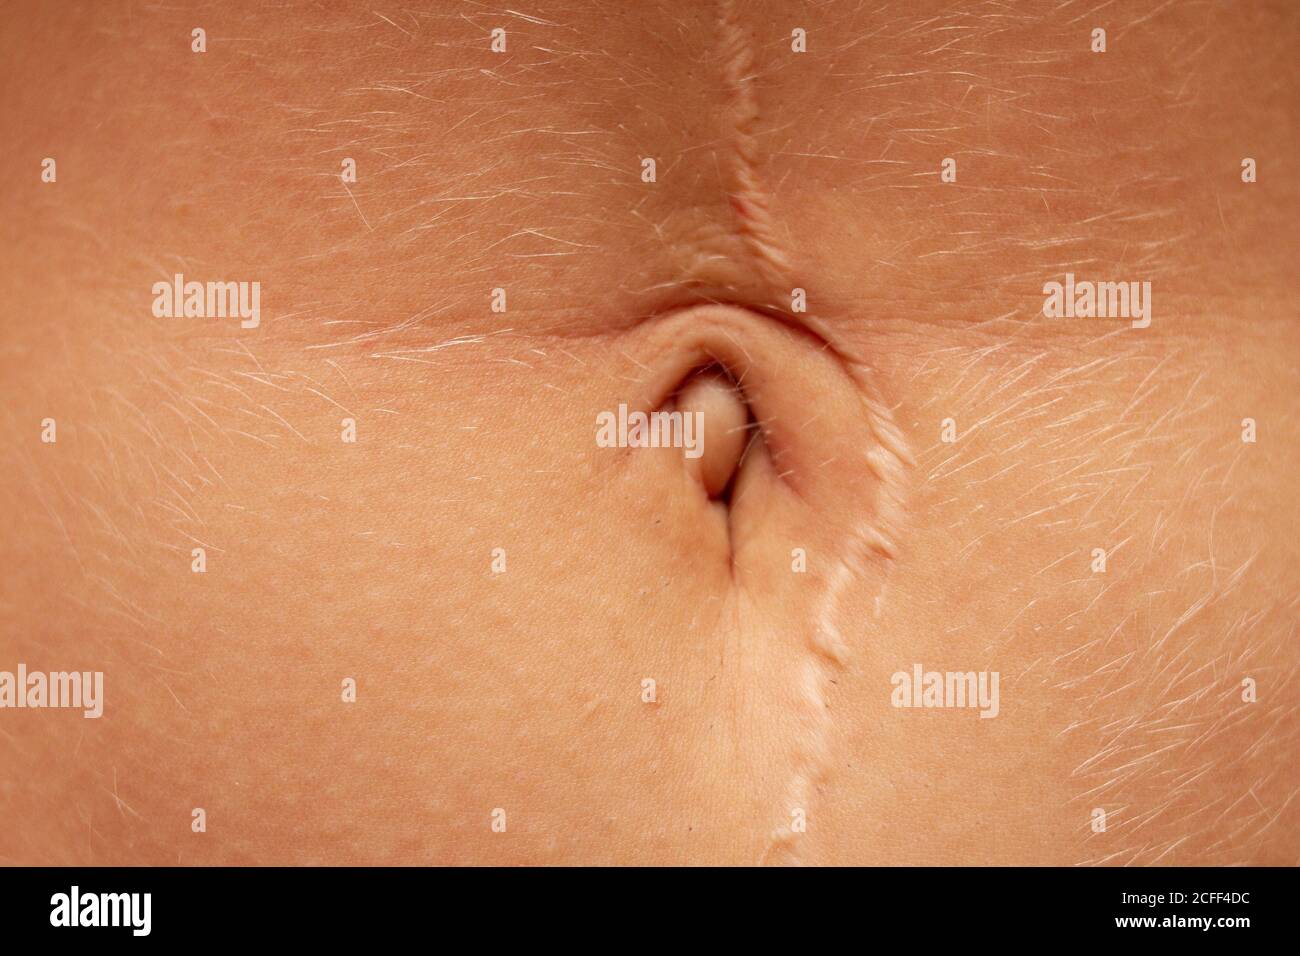

bouton de ventre de nombril femelle sur un estomac avec un grand cicatrice Banque D'Imageshttps://www.alamyimages.fr/image-license-details/?v=1https://www.alamyimages.fr/bouton-de-ventre-de-nombril-femelle-sur-un-estomac-avec-un-grand-cicatrice-image370970360.html

bouton de ventre de nombril femelle sur un estomac avec un grand cicatrice Banque D'Imageshttps://www.alamyimages.fr/image-license-details/?v=1https://www.alamyimages.fr/bouton-de-ventre-de-nombril-femelle-sur-un-estomac-avec-un-grand-cicatrice-image370970360.htmlRF2CFF4DC–bouton de ventre de nombril femelle sur un estomac avec un grand cicatrice